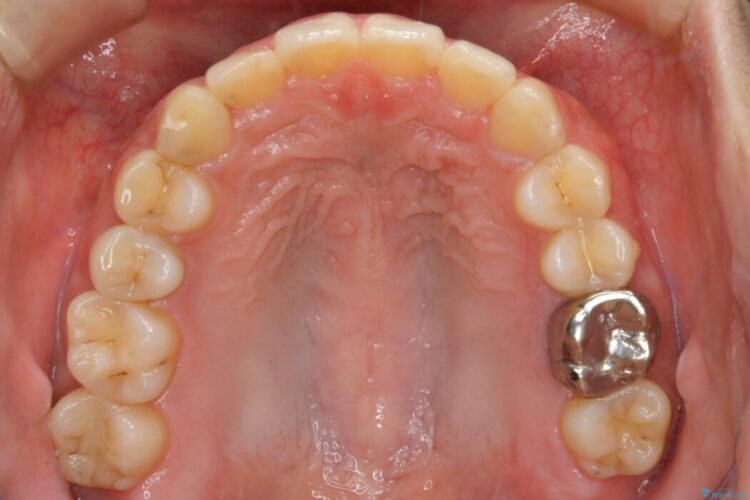

口ゴボに加えて歯列のガタガタを改善したいと来院されました。

患者様のご希望によりインビザライン装置での治療を行いました。

インビザラインは歯を後ろへ動かす動き、非抜歯での矯正治療が得意なため、ワイヤー装置では難しいケースでも対応できる場合があります。

矯正治療において歯並びを整えるためにはスペースが必要になります。

抜歯・歯列幅の拡大・IPR(歯と歯の間を少し削って小さくする)・歯の後方移動などでそのスペースを確保します。

程度にもよりますが口元を下げる治療というと抜歯治療を思い浮かべると思いますが、インビザラインは抜歯をせずとも他の3種類の方法を効率よく活用し治療ができます。